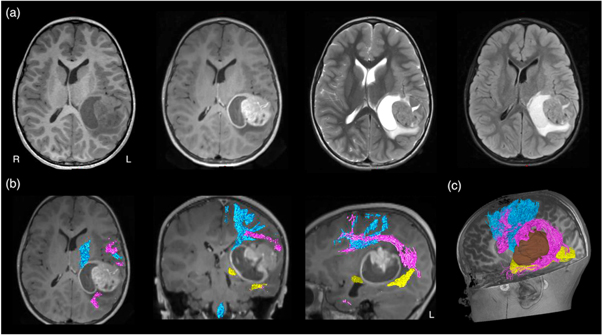

MRI-based neuroimaging is indispensable for modern neurosurgical practice, with critical roles in aiding pre-surgical planning and providing intraoperative imaging guidance (Upadhyay and Golby 2008, Enchev 2009). During surgery, the patient's head is co-registered with his or her preoperative MRI data using the image-guided neuronavigation software. Akin to a Global Positioning System, this enables subsequent intraoperative neuronavigation by accurately tracking the positions of the surgical instruments, and displaying these in relation to the patient's MRI dataset. Additionally, predefined image segmentations, such as the tumour volume, and the tractography images can be displayed into the operating microscope eyepiece, via augmented reality technology, and thus, be overlayed on the live microscope view as either semi-transparent or outlined objects (Kuhnt et al 2012, Sommer et al 2013). The ability to confirm the live resection view with MRI makes surgery more precise, while minimising injury to surrounding healthy brain structures. Conventional structural MRI sequences, such as T1-weighted, gadolinium contrast enhanced T1-weighted, T2-weighted, and fluid-attenuated inversion recovery (FLAIR) imaging, provide rich information concerning the relevant surgical anatomy. This includes demonstrating the regional surface sulcal-gyral and vascular anatomy, lesion extent, and the clarity of the tumour-brain interface. They also provide clues about pathological tissue properties and makeups, such as the presence of solid versus cystic component; the presence of acute intra-lesion haemorrhage; and suggestion of histopathologically high-grade tumour component with gadolinium-contrast enhancement. Despite being informative, none of these routine structural MRI sequences can depict the WM tract anatomy, specifically to demonstrate the tract disruption and/or displacement from its conventional trajectory, adjacent to the target surgical lesion (see figure 3(a)).

Figure 3. (a) Conventional structural MRI sequences (from left to right: T1-weighted, T1-weighted post-gadolinium contrast, T2-weighted, and FLAIR imaging) enable the characterisation of brain tumour and its effect on peri-lesion white matter. However, they were unable to demonstrate both the location and disruption of adjacent white matter tracts to the tumour; (b) diffusion MRI tractography aids pre-surgical planning and intraoperative imaging guidance by enabling in vivo mapping and visualisation of the corticospinal tract (in blue), arcuate fasciculus (in pink), and optic radiation (in yellow), demonstrating their spatial relationship with the tumour. All MRI are displayed in radiological orientation. (c): 3D rendered tractography images and tumour (segmented in brown). Material acronyms: L (left), R (right).

Standard image High-resolution imageWithout being able to delineate affected WM tract location under direct vision, direct brain electrical stimulation (DES) performed during surgery is widely accepted as the surgical 'gold standard' confirming the WM tract position and its functional relevance (more details about the DES procedure is described in Q&A 7) (Penfield and Boldrev 1937, Ojemann et al 1989, Berger and Hadjipanayis 2007, Duffau 2015). Pre-surgical localisation of intrinsic tumours and functional cortical regions may be achieved by multiple non-invasive imaging modalities, such as positron emission tomography (PET); single-photon emission computed tomography; blood oxygen level-dependent functional MRI (BOLD-fMRI); magnetoencephalogram (MEG); and navigated transcranial magnetic stimulation (nTMS). Diffusion MRI tractography remains the only non-invasive technique enabling visualisation of in vivo WM tract anatomy (Jones 2008a), making it a powerful technique to complement neurosurgical planning and intraoperative execution (figures 3(b) and (c)). Coupled dMRI tractography with functional brain mapping strategies, such as BOLD-fMRI, or with intraoperative DES findings can improve the functional relevance of tractography reconstructions and offer insights into brain structural-functional relationship between the cortical–subcortical structural networks and patient's functional states both before and after the surgery (Berman et al 2004, Kinoshita et al 2005, Bello et al 2008, Sanvito et al 2020) (more to this in Q&A 5).